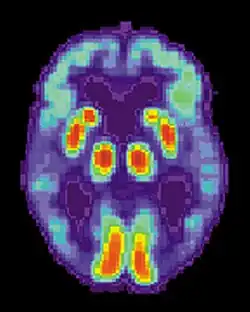

T. Awipi and L. Davachi sought to provide evidence of competing subregions in the medial temporal lobe (MTL) that differed on the type of content they encoded. The researchers conducted a study in which subjects were asked to perform an encoding task in a functional magnetic resonance imaging (FMRI) scanner, where they were presented with 192 full colour photographs of scenes (containing a centrally presented novel scene and a smaller image of one of six objects). Participants were also instructed to imagine using the presented object in each scene, and were asked to report whether they were successful. A memory test was administered after participants were removed from the scanner. The test consisted of all previously viewed scenes (old) and an equal number of novel scenes (new). They were asked to make an old/new judgement, and if the scene was responded as being old, they were asked to report it as being "remembered" or "familiar". They were then asked to pick an object that was paired with that scene. The researchers were trying to determine the levels of activation for source recollection for the objects paired with the scene during encoding.[18]

The researchers found that perirhinal cortex activation was greater for objects recalled, and parahippocampal cortex activation was greater when scenes were recalled.[18] The results provide evidence of distinct encoding activation in the subregions of the medial temporal lobe.[18] The first subregion is the perirhinal cortex, which encodes item information. The second subregion, the parahippocampal cortex, is involved in source information. The evidence provides support for the role of the right perirhinal cortex in attributing an object to the right source.[18] As decreased activation was associated with poorer performance, decreased activation of the right perirhinal cortex could be a possible mechanism for source confusion.